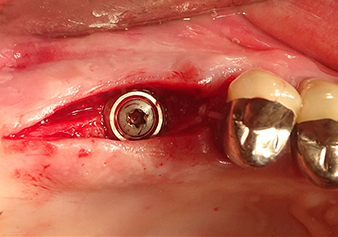

A 49-year-old female patient, a non-smoker and with nothing remarkable in her general medical history, was referred to our oral surgery practice for surgical extraction of tooth 16 and subsequent implantation. After the extraction, the patient experienced mild sinusitis trouble with the resultthat we initially waited six months before carrying out the measure. The residual bone height at the planned implant position measured 3-4 mm (Fig. 1 and 2).

Following atraumatic preparation of the mucoperiosteal flap, the implant position was marked with the I1 instrument and the site prepared – until initial resistance was felt. Piezosurgical instruments were used in an up and down movement without any pressure being exerted. The piezoelectric vibration produced the desired and efficient cavitation.

The I2A instrument (diameter 2.0 mm) was then used to perforate the sinus floor intermittently and on the smallest scale possible. This special piezosurgical method ensures that the Schneiderian membrane is not damaged. When the Z25P was used, the membrane was already lifted slightly by the coolant supplied via the instrument tip (Fig. 3). The coolant quantity was just 50% in order to avoid high pressure in the implant bed.